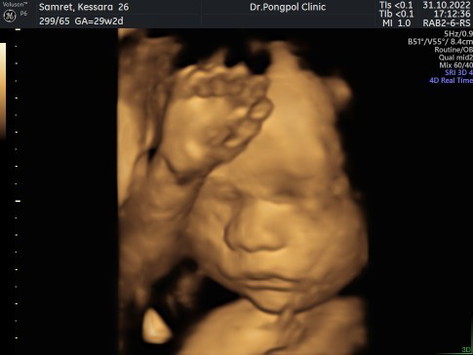

แตกกับเขาสักทีเด็กยาเร่งเต็มระบบ40+4 ประสบการณ์ที่ทรมานที่สุด

หมอนัดแอดมิทวันที่17 อายุครรภ์40+3 สิบโมงเช้าหมอให้กินเป็นยาทานก่อน อีกแก้ว12.30 ไม่มีการตอบสนองใดๆกับยา หมอมาตรวจภายในไม่มีการเปิดเพิ่ม น้องเอาหัวลงต่ำแล้ว จัดไปอีก2แก้ว ก็เงียบกริบ 5โมงเย็น เปลี่ยนเป็นให้ยาทางสายน้ำเกลือ เริ่มมีท้องแข็งถี่ขึ้น แต่ยังไม่ปวด จน4ทุ่มหมอมาตรวจเปิด2เซน และหัวน้องเลื่อนขึ้นสูงไปอีก แต่แม่คือเริ่มเจ็บถี่มาก 5ทุ่มและเริ่มปวดๆ น้องต่ำลงแล้วแต่ปากมดลูกเท่าเดิม หมอเลยช่วยเจาะถุงน้ำคร่ำหมอบอกพอน้ำเดินแล้วมดลูกจะเปิดเร็ว แล้วก็อัดยาให้เร็วขึ้นจาก40เป็น100 เที่ยงคืนเปิด3เซน แต่ปวดลงก้นแล้วคือทรมานมาก ตี1ครึ่งรู้สึกเจ็บมากขึ้น อยากเบ่งให้ออกๆให้ได้ ต้องหายใจทางปากแล้ว หมอเลยย้ายมาห้องคลอด ปากมดลูกเปิด5เซน เจ็บหนักจนบิดตัวไปมาพยาบาลก็คอยมาจับมือลูบแขนใก้แม่ค่อยหายใจ จนตี2อยู่ๆก็รู้สึกเหมือนมีอะไรดันออกมา หมอมาดูเจอหัวน้องแล้วกำลังเปลี่ยนชุดทำคลอด พยาบาลเพิ่งเตรียมของเพราะไม่คิดว่าเร็ว แต่พอแม่เจ็บท้องอีกทีเหมือนน้องจะดันออกมาเองคือแม่รู้สึกได้เลยว่าน้องออกมานิดนึงแล้ว หมอบอกอย่าเพิ่งเบ่งแม่หมอใส่ถุงมือแปป พยายามกลั้นสุดแรง พอหมอมาจับปุ้บแม่ปล่อยแรงเบ่งเต็มที่เลยทีเดียวคลอด รู้สึกโล่งแต่คือหมดแรงกับการเจ็บท้องหลายชม.จนพูดไรไม่ออก ท้องแรกคลอดเองง่ายมาก ท้อง2โดนยาเร่งตอนปากมดลูกเปิด5เซนทรมานแหละ แต่แค่3ชม.คลอด แต่ท้อง3ไม่มีอาการอะไรโดนยาเร่งตั้งแต่เริ่มทรมานสุดๆ แถมเสี่ยงตกเลือดอีก ต้องคลึงมดลูกต่อ ง่วงก็ง่วง เหนื่อยก็เหนื่อย ไม่เคยคิดจะผ่าคลอด วินาทีนั้นคือฉันไม่ไหวผ่าฉันเถอะ แต่หมอให้ทนอีกนิด ยังไงก็มาครึ่งทางแล้ว จบสิ้นแล้วการเร่งคลอด12ชม.ของฉัน #คลอด18/01/66อายุครรภ์ 40+4 หนัก3010